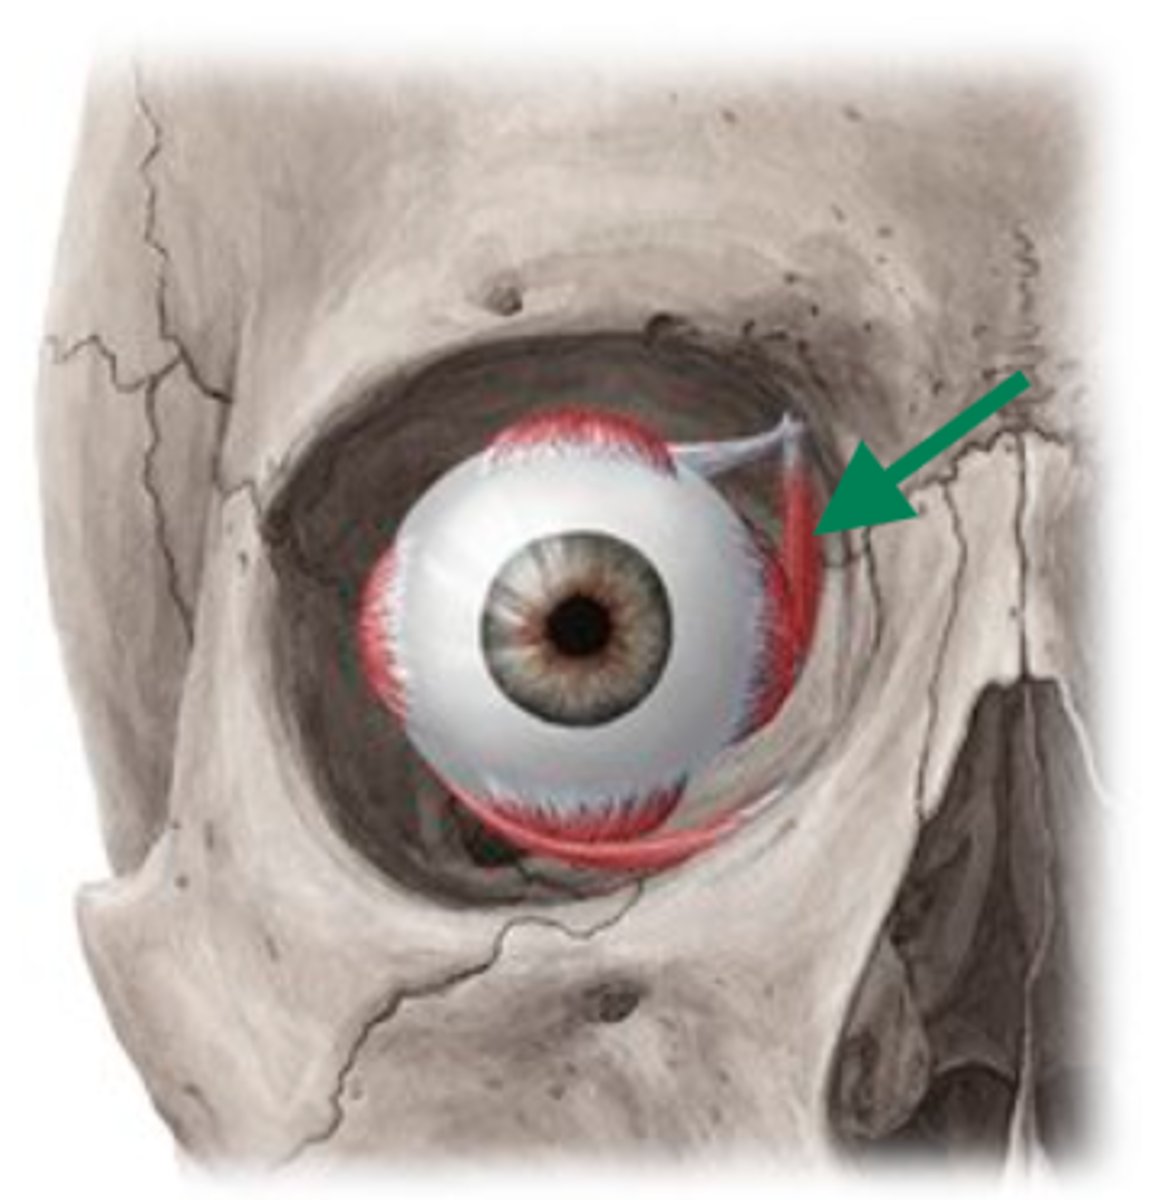

lateral rectus